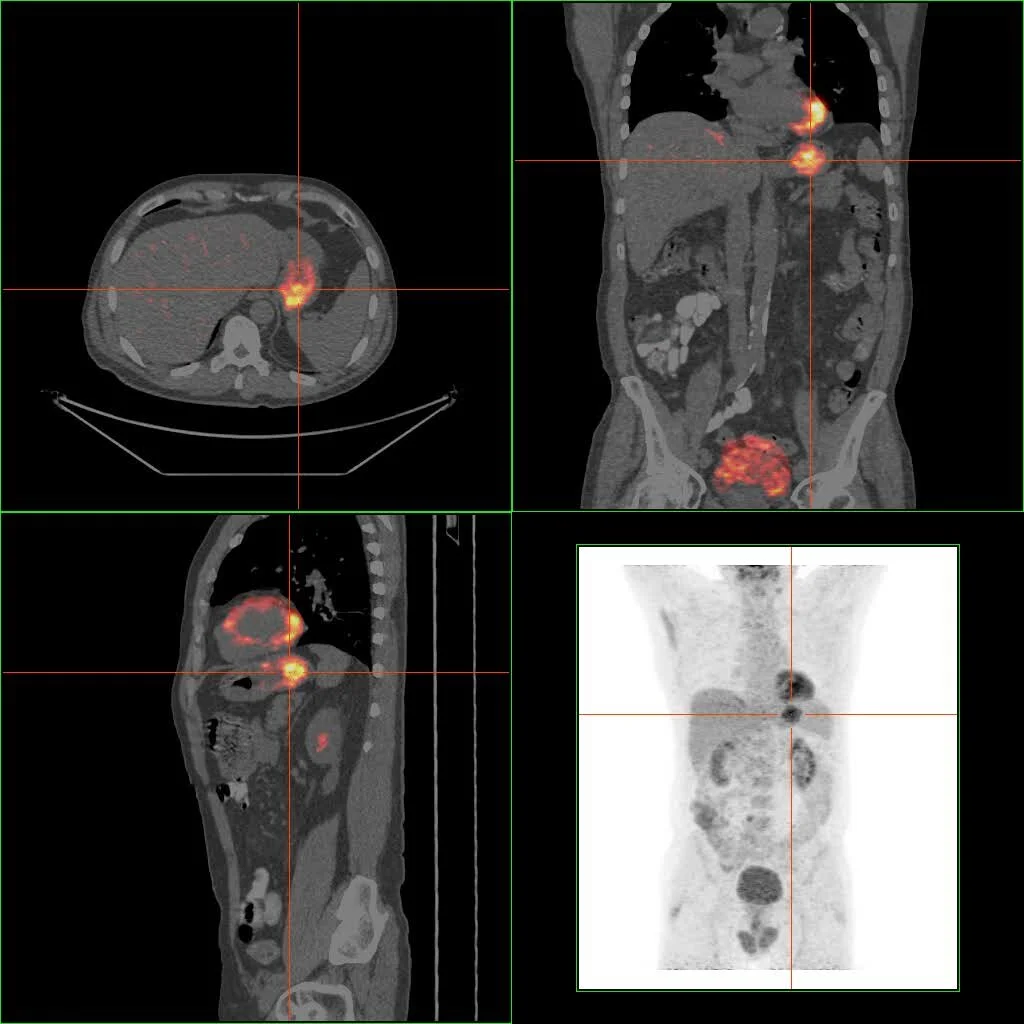

• Medicina nuclear

Se inyecta un componente radioactivo que se une a una molécula en específico, marcándola. Al hacerlo emite energía (rayos gamma comúnmente).

PET CT.jpeg

• Metabolismo

Finalmente, cuando es imagenología de metabolismo, es aquella que marca una proteína, encima o molécula en general con un componente radiactivo tolerable para el cuerpo humano con la intención de ver la ruta metabólica que dicha molécula pueda tener. En este ámbito se encuentra la tomografía por emisión de positrones (PET, por sus siglas en inglés). (The Essential Physics of Medical, 2012)